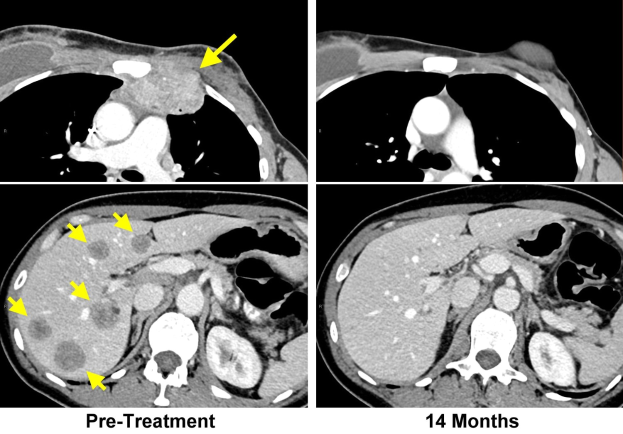

Eine CT-Aufnahme der Brust eines Patienten mit einem gelben Pfeil, der nach links zeigt, und einem schwarz-weißen Hirnbild mit der Beschriftung "vor der Behandlung" und "14 Monate" unten.